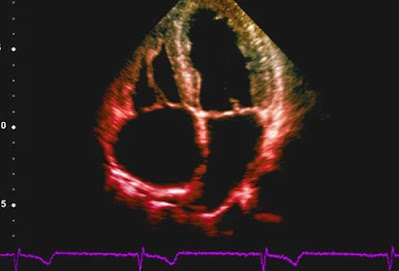

Έλεγχος καρδιακών παθήσεων: Ηχοκαρδιογράφημα

Το ηχοκαρδιογράφημα χρησιμοποιεί ηχητικά κύματα για να απεικονίσει την καρδιά.

Το ηχοκαρδιογράφημα είναι μια κινούμενη εικόνα πραγματικού χρόνου μιας λειτουργούσας καρδιάς που γίνεται με τη χρήση ηχητικών κυμάτων (υπερήχων) για τη δημιουργία εικόνων.

Τα ηχοκαρδιογραφήματα χρησιμοποιούν την ίδια μη επεμβατική τεχνολογία που χρησιμοποιείται για την εξέταση του εμβρύου κατά τη διάρκεια της εγκυμοσύνης. Μπορεί να δείξει πόσο καλά λειτουργούν οι καρδιακοί θάλαμοι και οι βαλβίδες της καρδιάς (για παράδειγμα, αποτελεσματική ή κακή δράση άντλησης, ροή αίματος μέσω των βαλβίδων), πριν και μετά τη θεραπεία, καθώς και άλλα χαρακτηριστικά.